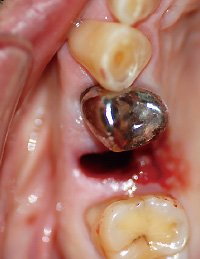

抜歯および周囲病変部の摘出を局所麻酔下に行った。鉗子にて

を抜歯後、周囲の肉芽様組織の掻爬を行った。大小さまざまな複数の茶褐色の硬固物が歯根に付着していた(図❸❹)。抜歯窩骨面は正常で、上顎洞への交通なども認めなかった。摘出物は、病理組織検査に提出し、炎症性肉芽組織および歯石との診断を得た(図❺)。

図❸ 術中写真、5抜歯窩